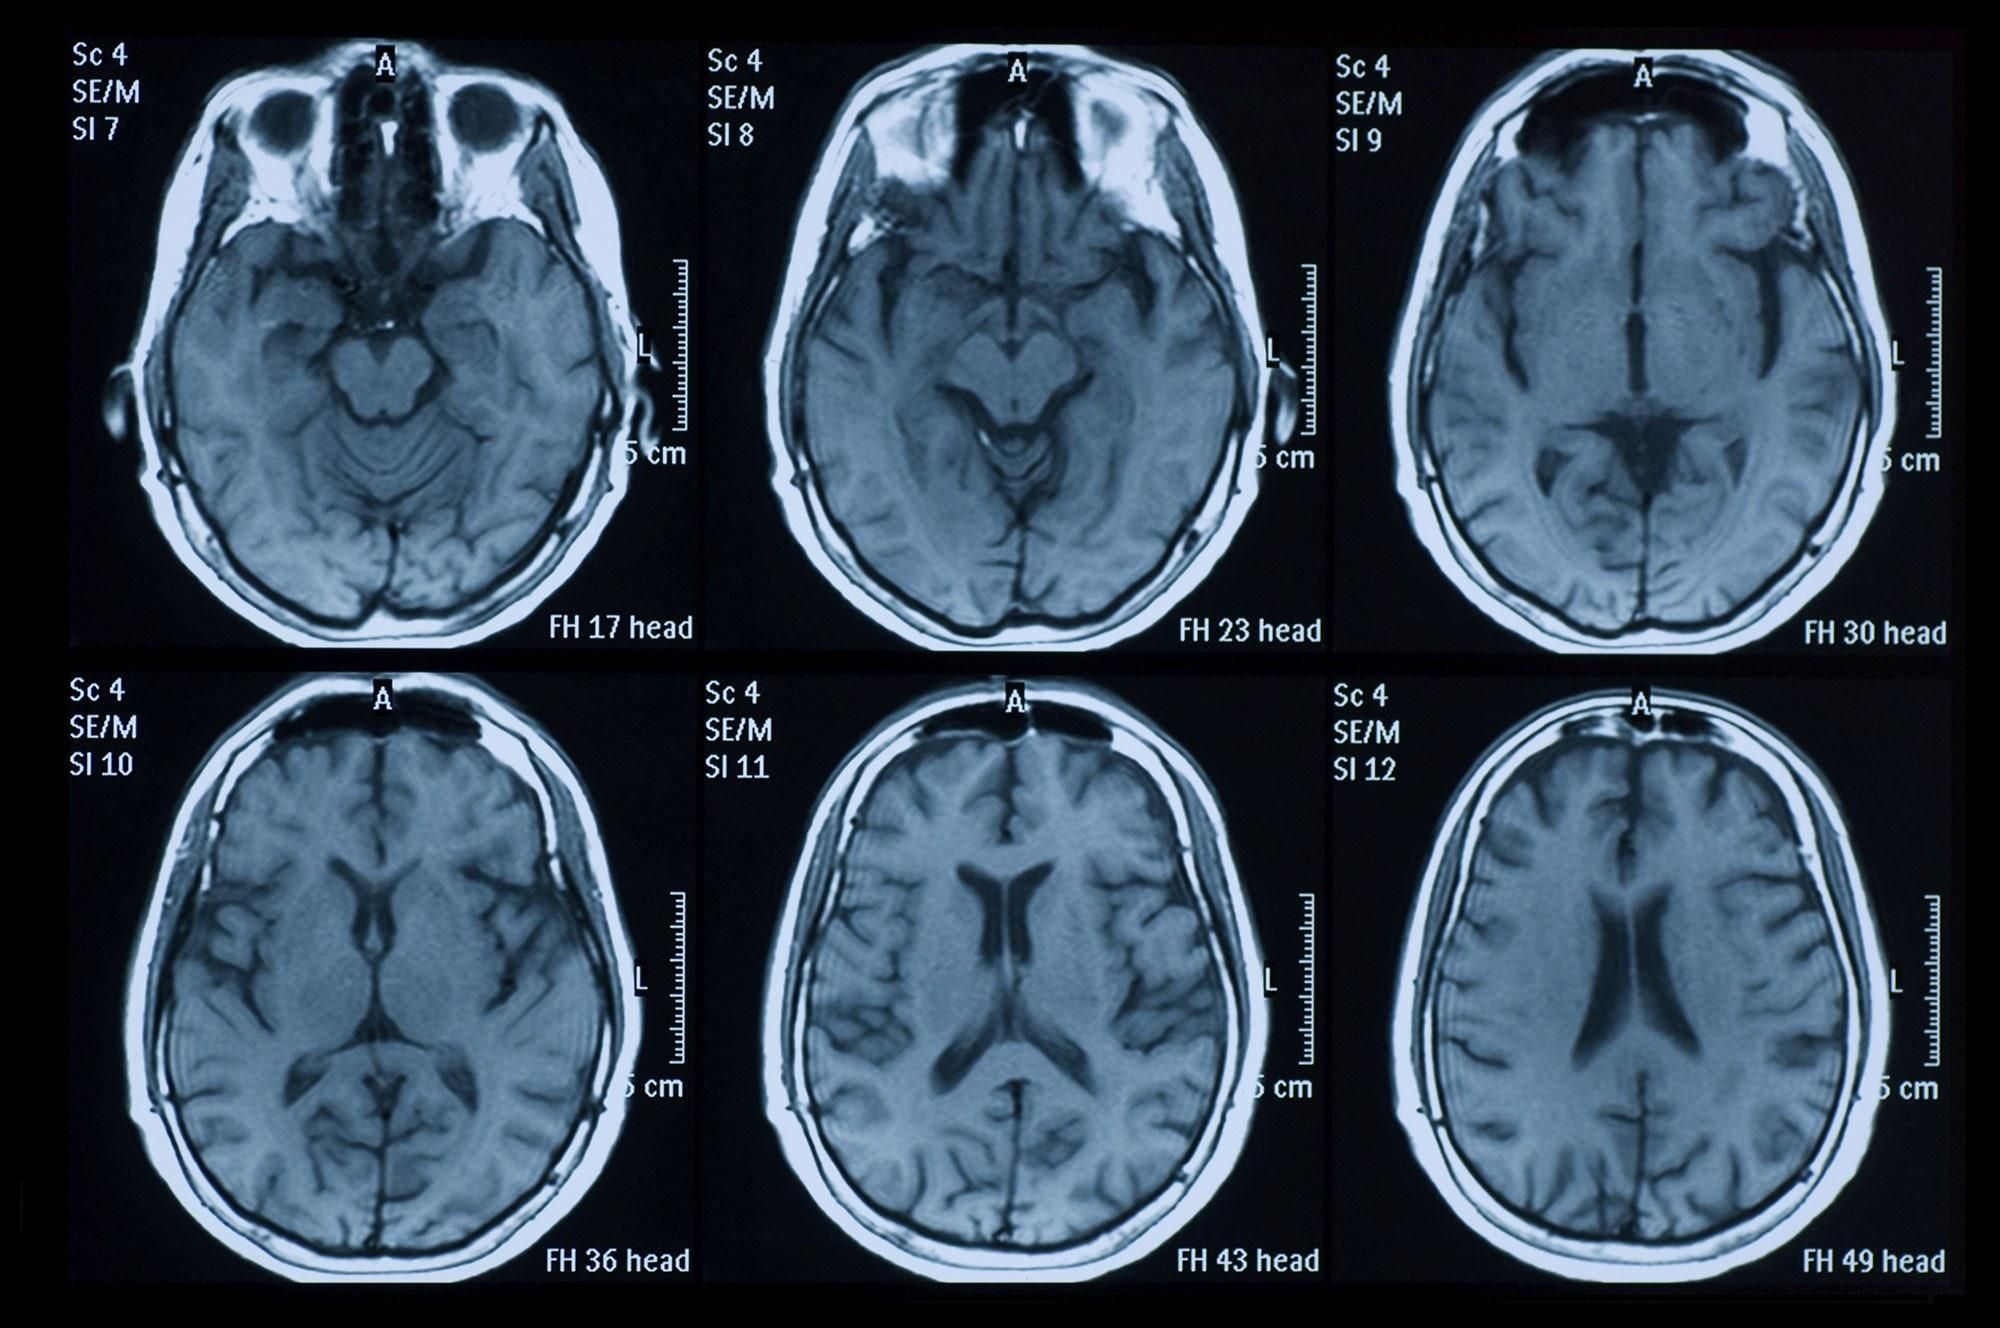

Сообщается о 74-летнем мужчине и 58-летней женщине, которые заболели коронавирусом и перенесли неврологические расстройства. Сканы мозга женщины продемонстрировали уменьшение плотности мозгового вещества и кровотечения. При этом в больницу ее доставили в летаргическом состоянии, со спутанностью сознания и дезориентацией.

Врачи обнаружили смерть клеток и кровотечения мозга, в отделах, которые отвечают за ощущения, память, сознание и передачу сенсорной информации. Эти повреждения произошли в результате отека мозга – энцефалита, который также наблюдается у некоторых тяжелых больных гриппом и ветрянкой.

COVID-19 вызывает кровотечения в мозге / unsplash.com

Пока среди миллиона пациентов с коронавирусом лишь очень небольшое количество имеет неврологические осложнения. Но сколько их на самом деле неизвестно, потому что сканирование мозга всем пациентам не проводятся, и в стандартный протокол они не включены.